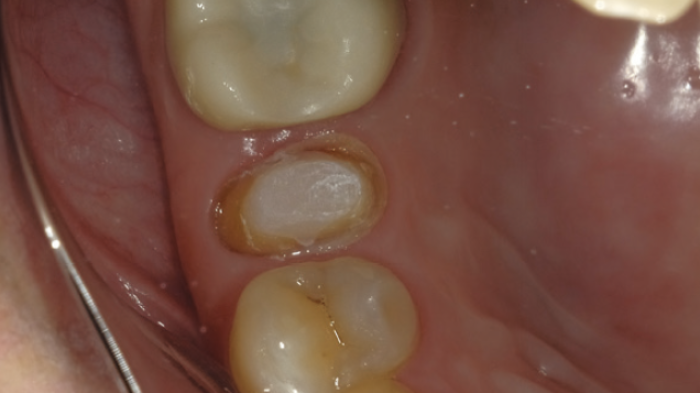

Etat de surface après le retrait de la restauration provisoire.

Sablage de la surface de l'ancrage. La pulvérisation d'eau aide à contrôler les particules d'oxyde d'alumine. Cela permet également de minimiser la contamination dans la cavité buccale. La pulvérisation de la poudre d'aluminium est maîtrisée par le spray d'eau. Cette procédure prévient également la contamination dans la salle de consultation.